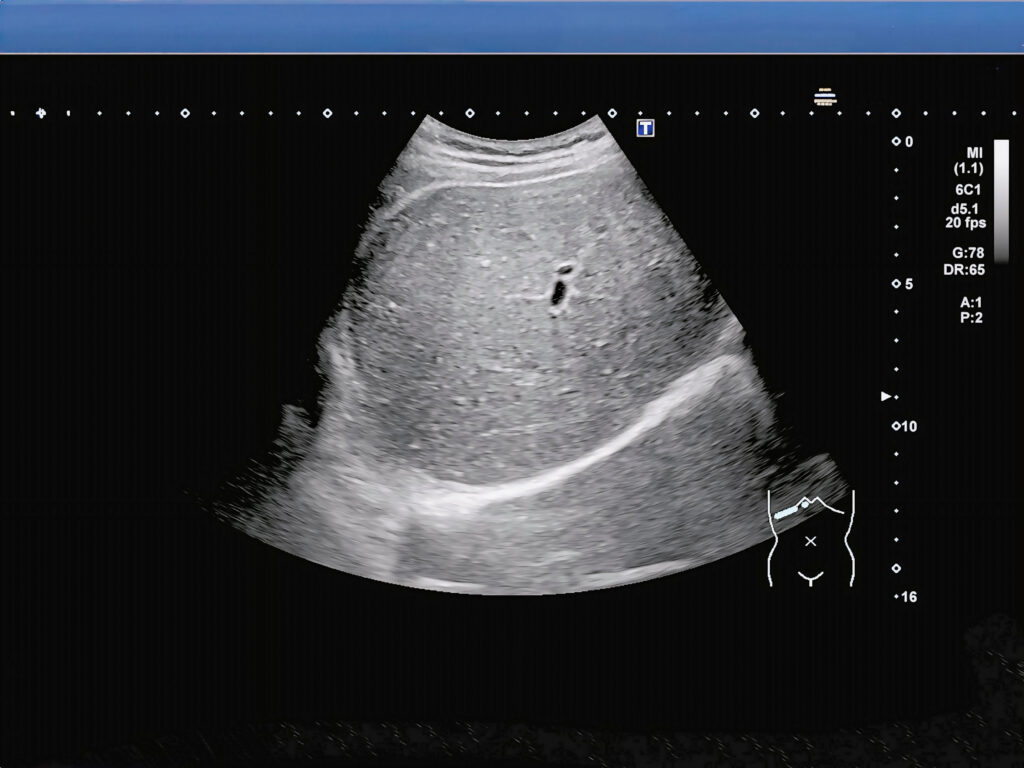

・腹部エコー(超音波検査)